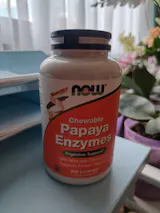

Много съм доволна от таблетките. Благодарение на тях нямам тежест и подуване след хранене.